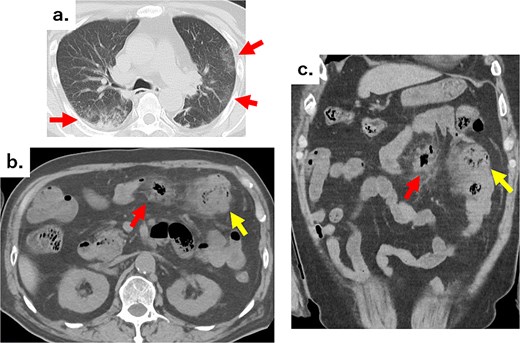

An 82-year-old man visited the emergency department with a chief complaint of slurred speech. There were no digestive symptoms, such as diarrhea, malabsorption, bloating, chronic abdominal pain, or internal bleeding. His respiratory and circulatory dynamics were stable, and the blood test results were as follows: White blood cell (WBC) 12 200/mm3, Hgb 11.3 g/dl, blood urea nitrogen (BUN) 27.4 mg/dl, Cre 1.65 mg/dl, C-reactive protein (CRP) 7.79 mg/dl, no abnormalities in liver function, and no biliary system elevations. Computed tomography (CT) revealed chronic bilateral subdural hematomas (Fig. 1). Normal neck-to-pelvis CT revealed mild bilateral pneumonia (Fig. 2a). Moreover, multiple diverticula were found, primarily in the upper small intestine. Two abscesses showing increased density of the surrounding fatty tissue were identified: one was a 5-cm abscess in the mesentery of the small intestine and the other had air in the mesentery on the distal side (Fig. 2b and c). As there were no obvious signs of perforation and the patient's vitals were stable, conservative treatment was also an option, but the formation of a 5-cm abscess within the mesentery was a difficult location to puncture under CT guidance; therefore, we opted for emergency surgical treatment.

(a) Chest CT showing reticular shadows in both lung fields (arrows). (b) Axial and (c) coronal abdominal CT images showing scattered jejunal diverticula, abscesses in part of the mesentery (arrows), and an air formation with increased density in the surrounding fatty tissue (arrows).